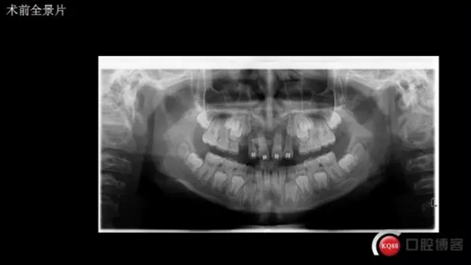

三年半前,家長領(lǐng)著小孩前來要求矯正牙齒,男,約八歲,兩中切牙間隙約12MM,有一多生牙,全景片顯示深處還橫著一顆,也許正處叛逆期,小孩非常的調(diào)皮,經(jīng)過幾次的各種哄和商談,也可能為了好看,終于勉強同意先拔掉露出的多生牙,前牙片斷弓關(guān)閉間隙

CBCT術(shù)前分析,精準找到牙齒的具體位置